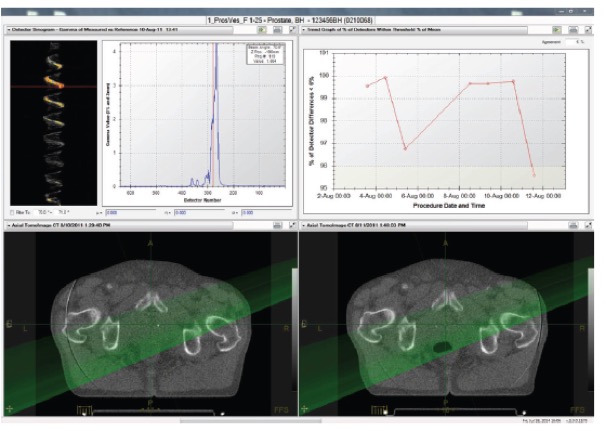

I. Delivery Analysis

Το σύστημα Delivery Analysis επεξεργάζεται με τρόπο αυτόματο τα δεδομένα από την εκτέλεση της θεραπείας κάθε ασθενούς και ελέγχει αν κάθε συνεδρία αποδίδεται όπως έχει σχεδιαστεί.

- Για κάθε ασθενή, το Delivery Analysis ελέγχει τη σωστή λειτουργία του κατεθυντήρα πολλαπλών φύλλων χρησιμοποιώντας το σήμα του ενσωματωμένου ανιχνευτή του συστήματος TomoTherapy. Σε περίπτωση εμφάνισης διαφορών το σύστημα αυτόματα υπολογίζει την επίδραση τους στην κατανομή της χορηγούμενη δόσης και ειδοποιεί τον ακτινοφυσικό και τον ιατρό.

- Σε κάθε συνεδρία το σύστημα μετράει και επεξεργάζεται την ροή φωτονίων στην έξοδο του ασθενούς (exit fluence) για να εξασφαλίσει την σωστή εκτέλεση της θεραπείας από την πρώτη έως την τελευταία συνεδρία.

Εύχρηστο περιβάλλον εργασίας

- Το σύστημα Delivery Analysis αναλύει τα δεδομένα από την εκτέλεση της θεραπείας και τα παρουσιάζει με τρόπο άμεσο και ευανάγνωστο στους ακτινοφυσικούς και του ιατρούς του τμήματος. Το σύστημα ενσωματώνει εργαλεία για την λεπτομερή εξέταση όλων των επιμέρους στοιχείων της θεραπείας συμπεριλαμβανομένων της ακρίβειας τοποθέτησης του ασθενούς, την επίδοσης του συστήματος TomoTherapy κτλ.

Ποιοτικός έλεγχος της ακρίβειας χορήγησης της θεραπείας

- Κατά την διάρκεια εκτέλεσης κάθε συνεδρίας και για κάθε ασθενή το σύστημα Delivery Analysis μετράει αυτόματα με τον ενσωματωμένο ανιχνευτή την ροή των φωτονίων στην έξοδο του ασθενούς

- Το σύστημα Delivery Analysis αναλύει και επεξεργάζεται αυτόματα την ροή των φωτονίων στην εξόδου του ασθενούς ώστε να εξασφαλίσει την σωστή εκτέλεση κάθε συνεδρίας της θεραπευτικής αγωγής του κάθε ασθενούς.